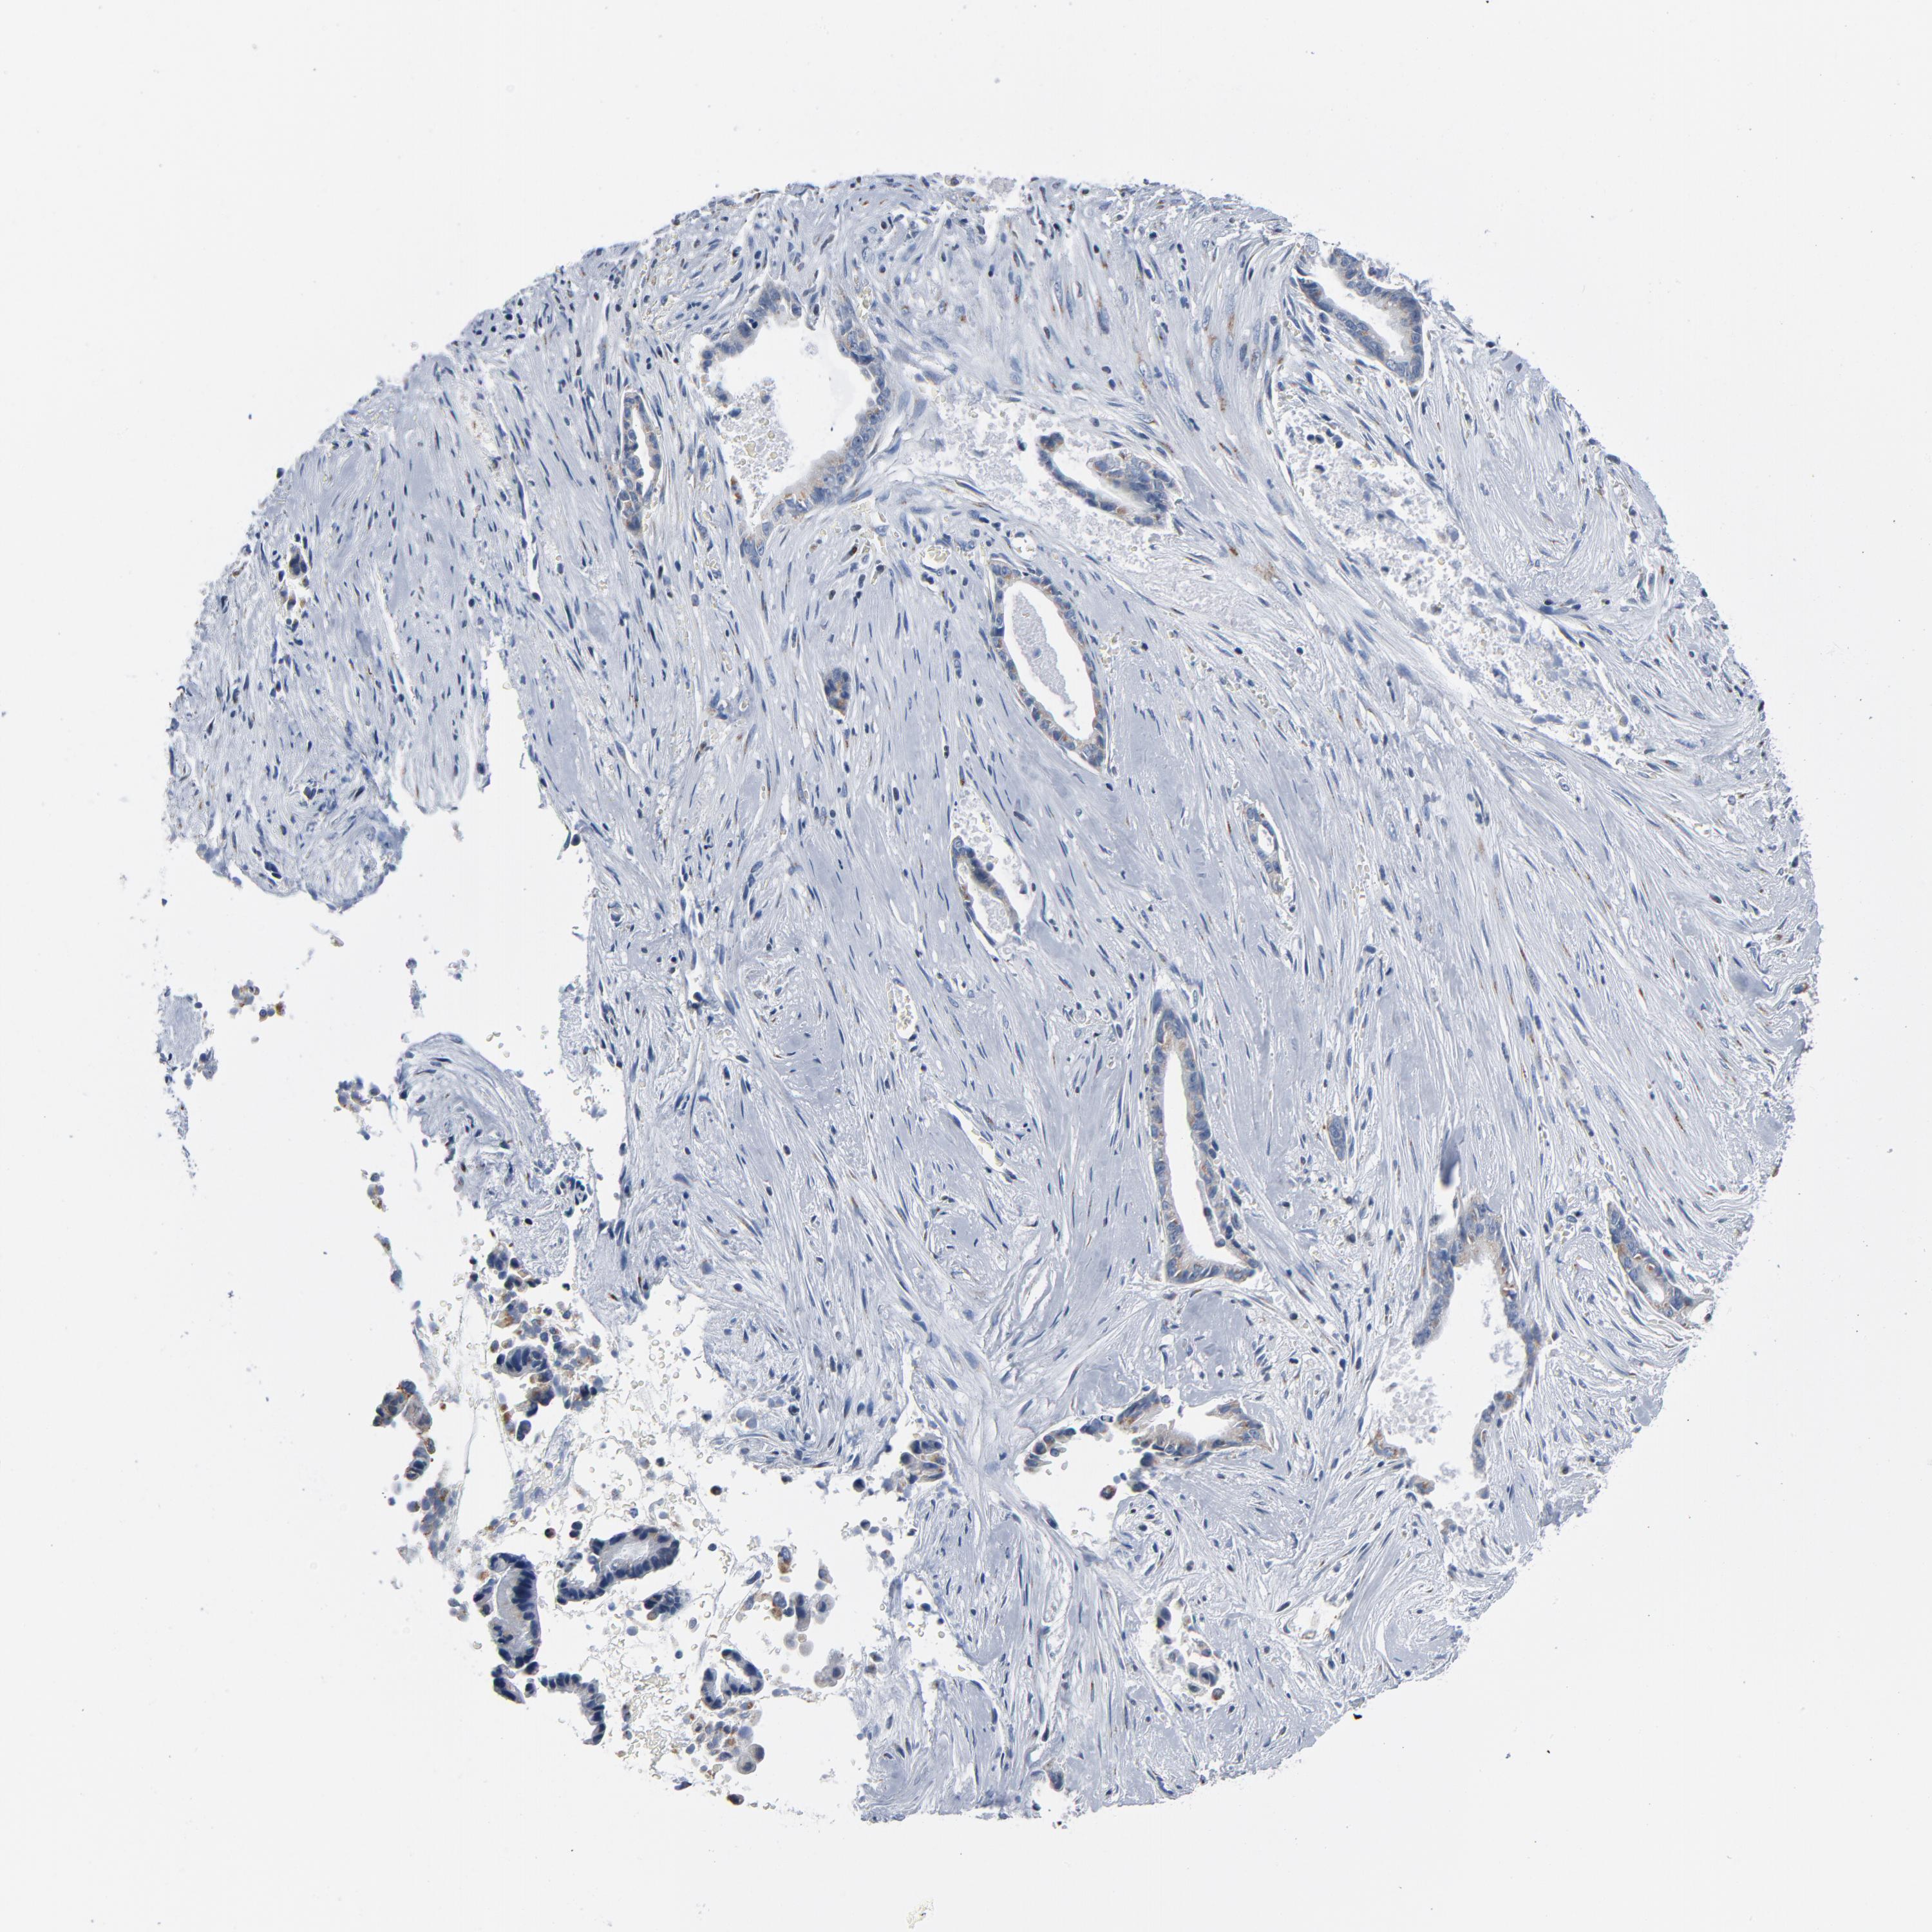

LIVER CANCER - Protein expressioni

A mouse-over function shows sample information and annotation data. Click on an image to view it in a full screen mode. Samples can be filtered based on level of antibody staining by selecting one or several of the following categories: high, medium, low and not detected. The assay and annotation is described here.

Note that samples used for immunohistochemistry by the Human Protein Atlas do not correspond to samples in the TCGA dataset.

Antibody stainingi

Antibody staining in the annotated cell types in the current human tissue is reported as not detected, low, medium, or high, based on conventional immunohistochemistry profiling in selected tissues. This score is based on the combination of the staining intensity and fraction of stained cells.

Each image is clickable and will lead to virtual microscopy that enables deeper exploration of all samples and also displays staining intensity scores, fraction scores and subcellular localization as well as patient and tissue information for each sample.

Antibody HPA003720

Staining

High

Medium

Low

Not detected

Intensity

Strong

Moderate

Weak

Negative

Quantity

>75%

75%-25%

<25%

None

Location

Nuclear

Cytoplasmic/membranous

Cytoplasmic/membranous,nuclear

Cholangiocarcinoma

Carcinoma, Hepatocellular, NOS